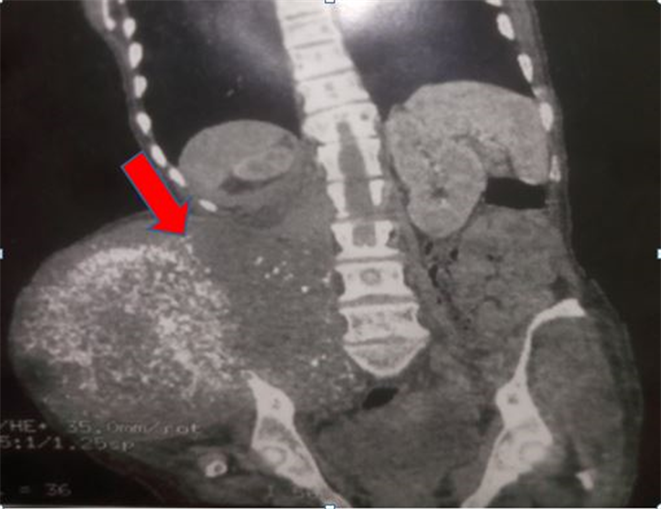

Five patients had preoperative abdominal computed tomography scan that objectified a collection in the right iliac fossa measuring 63 × 68 × 90 mm which was in contact with the right colon and ipsilateral Psoas muscle. It is shown in Figure 1. This collection was found to be probably originating from the appendix. One patient had a large hypodense collection (12 cm in height) in the right iliac fossa extending to the ipsilateral Psoas iliacus muscle as well as on the right anterolateral abdominal wall. A lateral uterine mass was found in a patient; it was an irregular polylobed mass in the right iliac fossa with a necrotized center narrowing the digestive lumen measuring 121 × 69 mm. Another patient had dilated loops of small bowel distension proximal to an irregular and circumferential thickening of the last segment of the ileum. The CT scan of a patient who underwent appendectomy was normal.

All patients received adjuvant chemotherapy. During follow up, carcinosis occurred in two patients and a locoregional recurrence in 2 other patients (Figure 2). Two patients never returned for follow-up.

Figure 2. Image of tumor recurrence (the arrow shows the tumor recurrence with invasion of the right iliac bone and anterolateral abdominal wall).